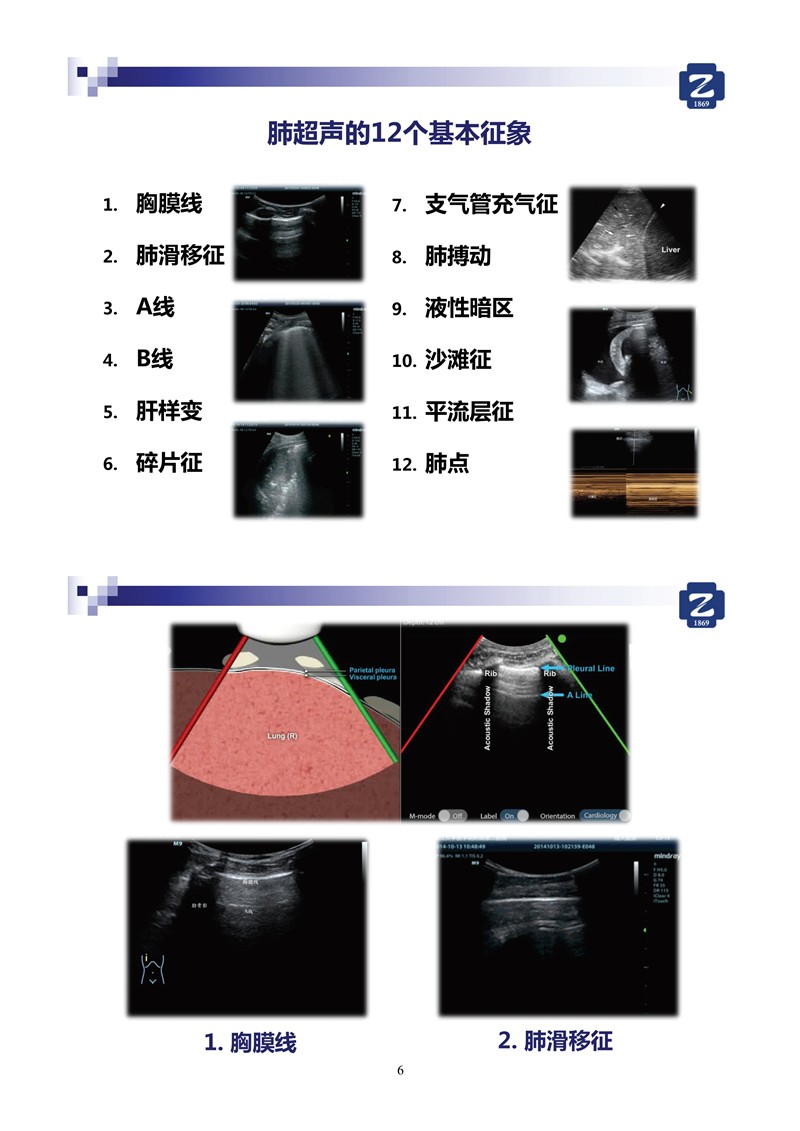

新冠肺超聲實用手冊(2)_35.jpg